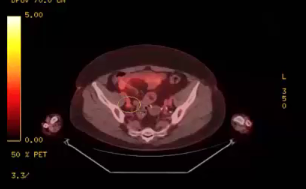

endometrial adenocarcinoma, para-aortic nodes, PET CT, diabetes, charcot arthropathy, groin nodes, pelvis, negative cervical margins, cisplatin, small bowel, Harkenrider, contouring, MRI, tumor, vaginal bleeding, relapse, persistence, cylinder, dose distribution, dosimetry, brachytherapy, fractio...

squamous cell carcinoma, dysplasia, PET, SIB, brachytherapy, endocervical, MRI, nodal location, inguinofemoral, right external iliac, CTV, deescalation, dosimetry, sigmoid, hysterectomy, concurrent chemoradiation, stenotic cervix, abdominal infection, external planning, avoid structure, antibioti...

chemotherapy, radiation therapy, sandwich regimen, brachytherapy, well differentiated endometrioid adenocarcinoma, neoadjuvant chemotherapy, small bowel, dilation, dosimetry, gross disease dose, MRI, cirrhosis, external beam radiation, Rotte Y applicator, CT scan, dual tandem, 3-D printing, endom...